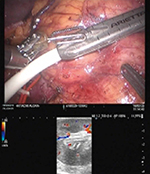

(3) 腎動脈をクランプし遮断後の腎血流を確認(図4)

図4 腎血流の確認 |